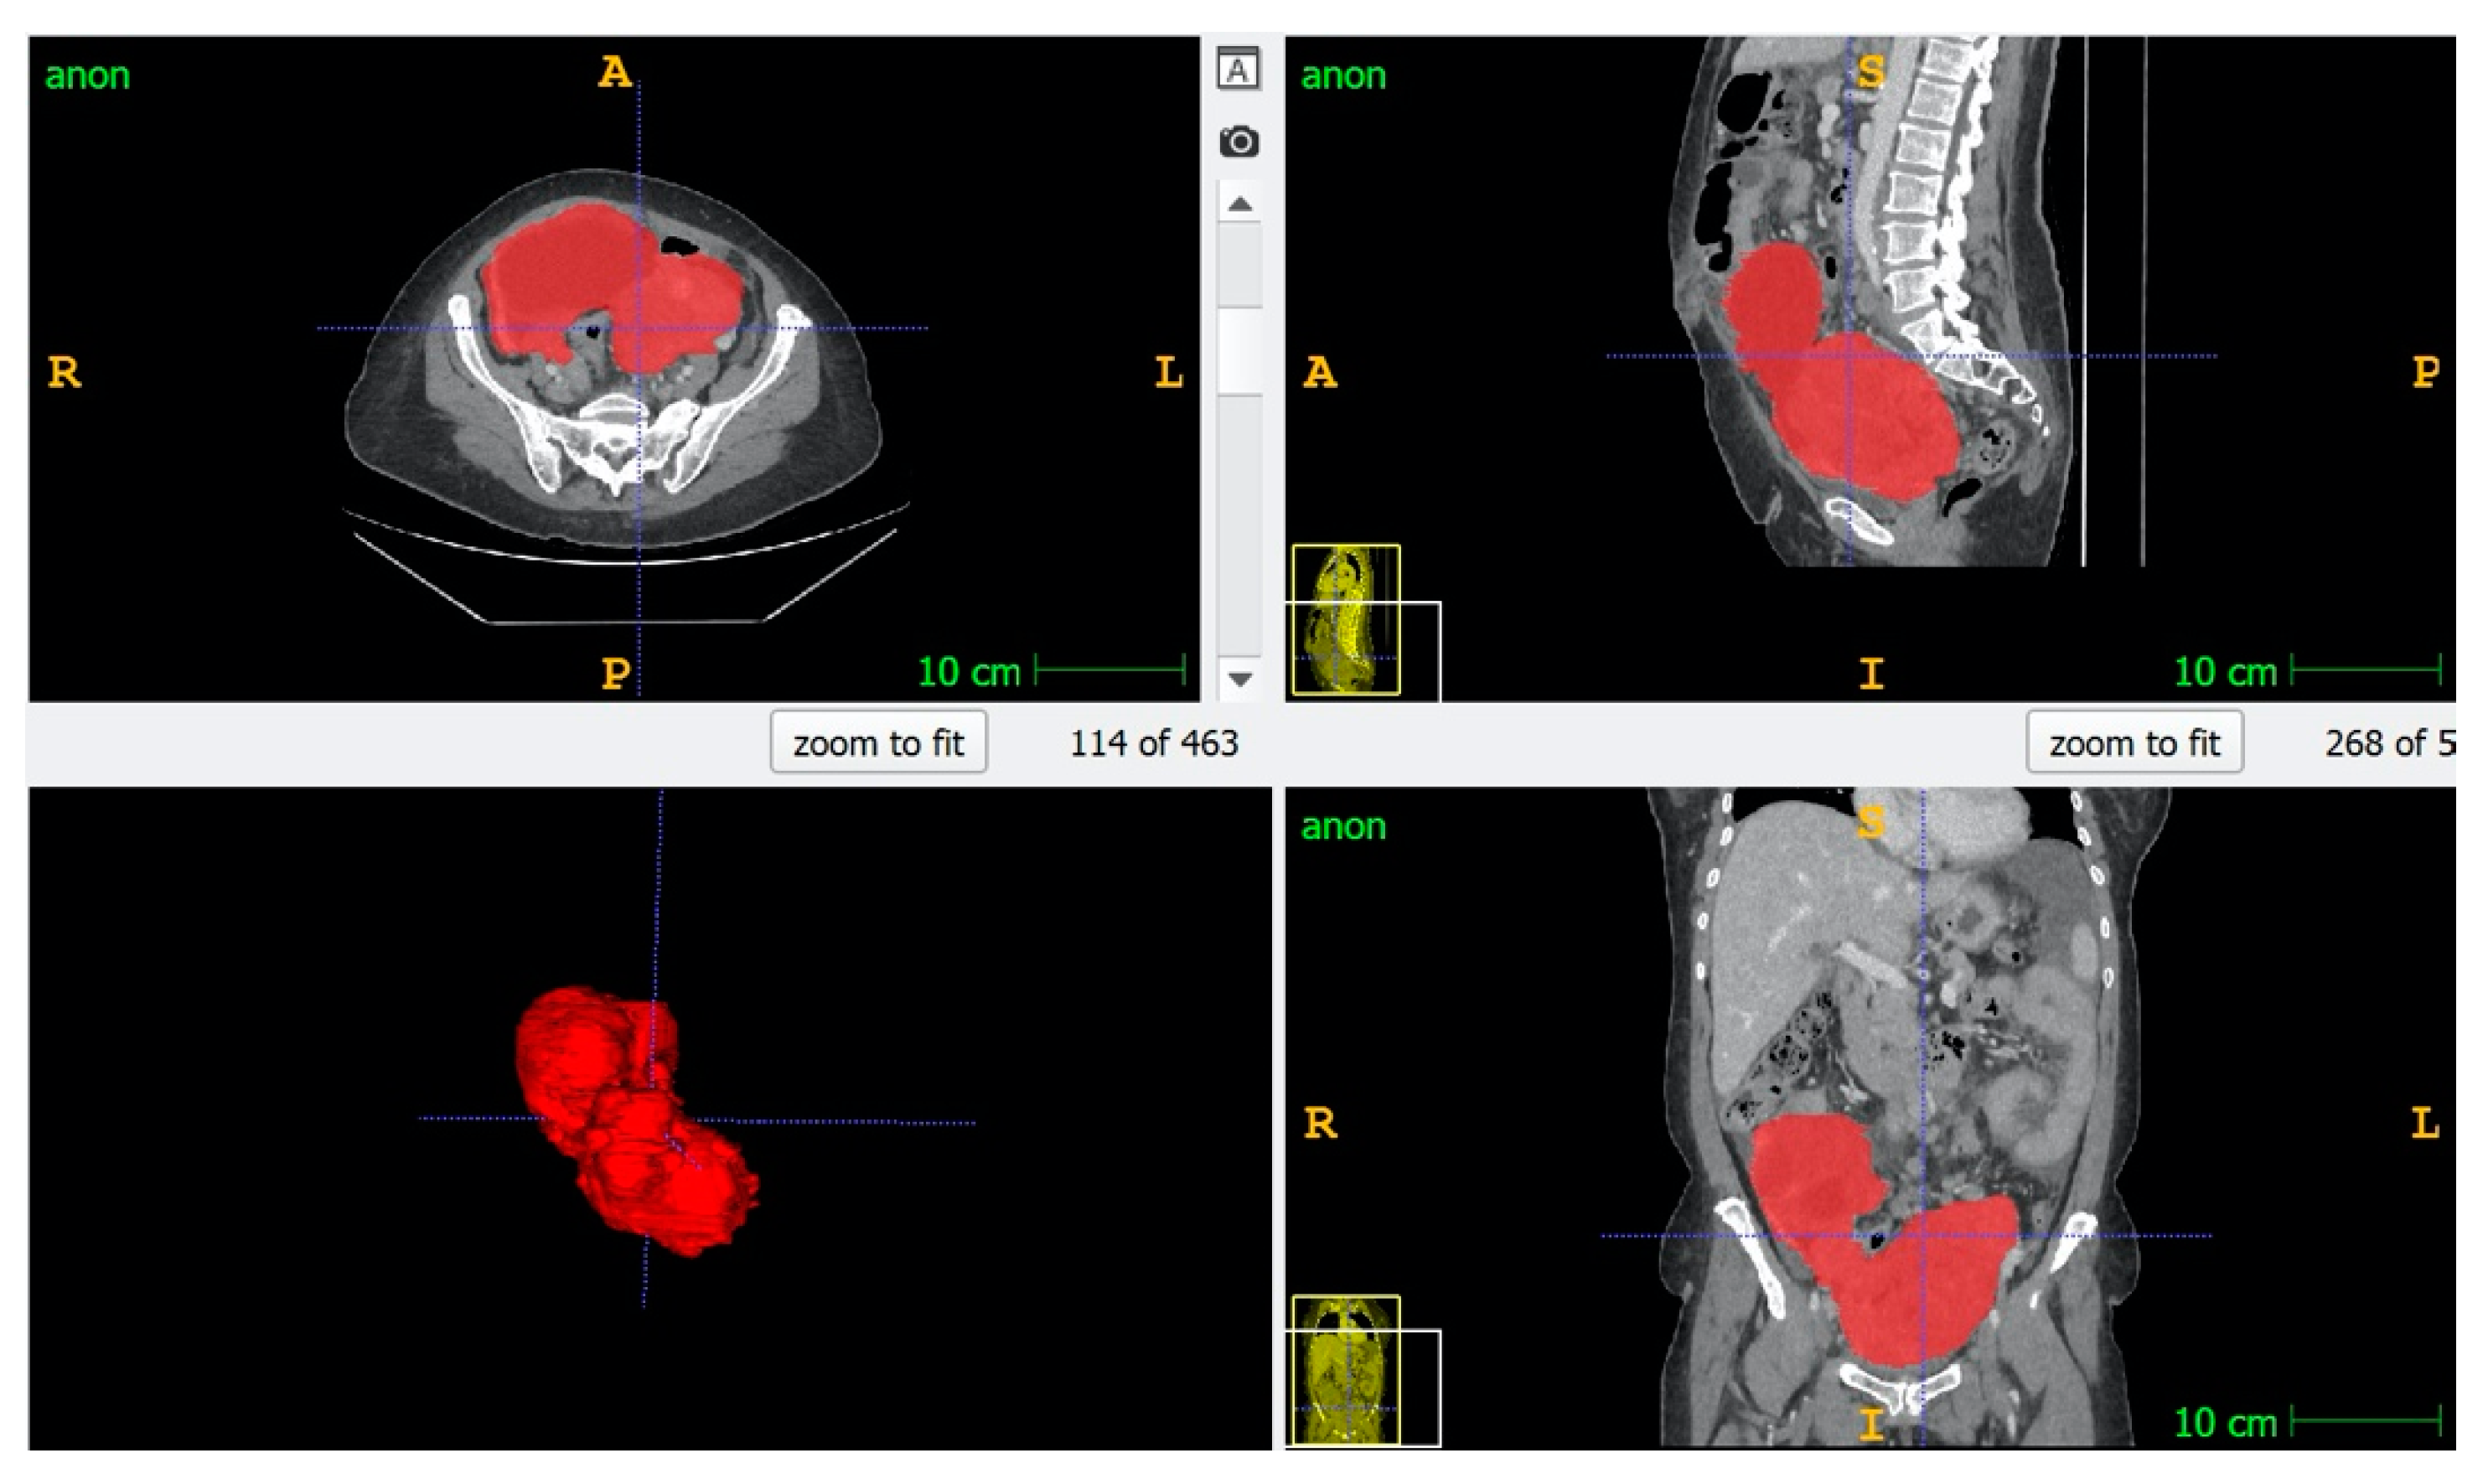

2.4. Image Segmentation